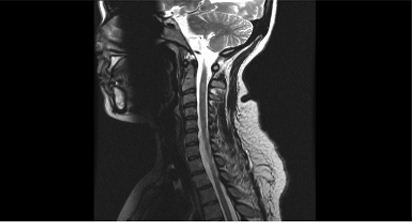

These MRI images depict the brain (top) and spinal cord (bottom) of a patient with multiple sclerosis of 10 years duration who recently transitioned from a relapsing-remitting to a secondary progressive course. The fluid-attenuated inversion recovery (FLAIR) imaging of the brain shows confluent disease typical for MS, with periventricular and juxtacortical lesions. The spinal MRI shows a lesion in the cervical cord, which is commonly seen in MS.

Images and case courtesy of Aliza Ben-Zacharia, DrNP, ANP-BC